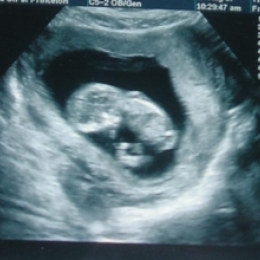

Что может показать УЗИ плода?

Установление беременности и оценка ее развития на ранних сроках - одна из главных задач УЗИ в акушерстве.

Сегодня УЗИ является единственным методом, позволяющим объективно наблюдать за развитием эмбриона с самых ранних этапов его развития. Использование эхографии в 1-ом триместре (1-12 недели) беременности дает более ценную информацию по сравнению с клиническими и гормональными методами исследования.

УЗИ - диагностика беременности возможна с самых ранних сроков (5-6 неделя от первого дня последней менструации). В отдельных случаях возможно выявление плодного яйца уже на 12-15-й день от момента зачатия.

Оценка жизнедеятельности эмбриона основывается на регистрации его сердечной деятельности и двигательной активности. В настоящее время можно осуществлять регистрацию сердечной деятельности эмбриона с 5 недель от момента зачатия. Двигательная активность эмбриона начинает выявляться при ультразвуковом исследовании с 8 недель беременности.